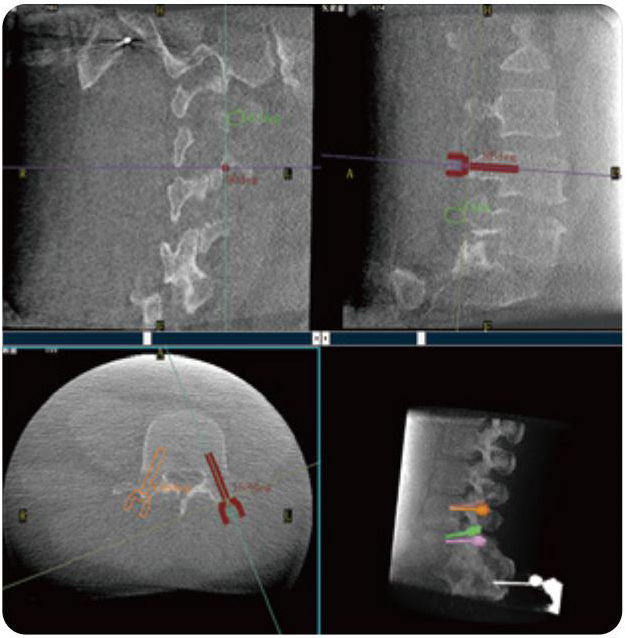

Clinical picture

临床图片